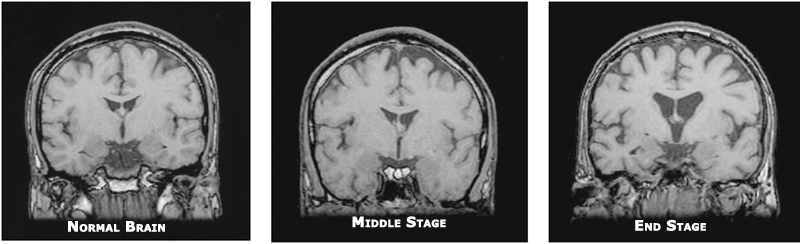

At least 1/3 of all sufferers diagnosis with early-onset dementia have Alzheimer’s Disease (remember that Alzheimer’s Disease is a type of dementia, but is not inclusive of all types of dementia, just as all photocopiers are not Xerox photocopiers and all facial tissues are not Kleenex facial tissues).

Onset symptoms include progressive and episodic memory loss, as well as visuospatial and perceptual deficiencies, but intact language and social functioning.

This type of early-onset dementia is more common in women than men. Once symptoms appear, the duration of the disease averages eight years.